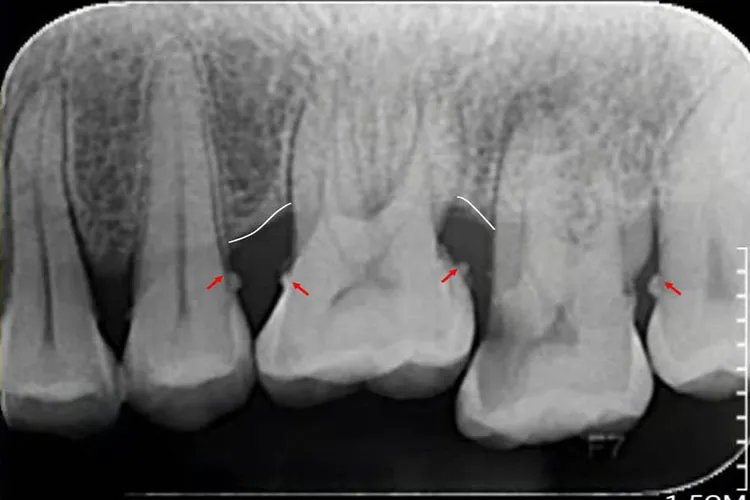

概述牙结石又称牙石,是附着在牙面上钙化的牙菌斑,外观呈白色、棕色或黑色。牙结石的形成主要受唾液成分、饮食习惯、口腔卫生习惯影响。症状牙结石初期较软,因逐渐钙化而变硬,外观呈白色、棕色或黑色,可分为龈上结石和龈下结石。龈下结石牙肉眼不可见,需用探针或X线检查可见。结石过多可刺激牙龈,导致牙龈萎缩,出现牙龈出血、牙齿松动等症状。

病因牙结石是由牙齿表面附着的食物残渣及唾液中的矿物质、坏死脱落的上皮细胞、白细胞等与黏液素以及涎蛋白和脂类混合形成的。口腔卫生习惯不良、常吃细软精细食物、摄入蔗糖过多等都是诱发牙结石的重要因素。诊断主要根据患者的临床表现,以及在口腔内见到牙结石作出诊断。龈下结石可通过探针或X线检查来进行诊断。治疗保持口腔良好的卫生,坚持刷牙漱口,可将刚开始沉积于牙面的牙垢、牙结石及时刷掉。要少吃精细食品,或吃后必须刷牙漱口。还可采用超声波治法去除牙结石,如龈上洁治法、龈下刮治疗法等。